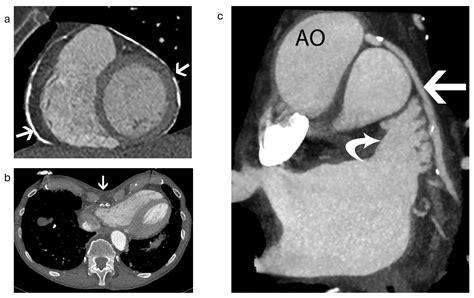

The most common method for the closure of left atrial appendage is a catheter-based, minimally invasive approach. During the procedure, the patient is placed under general anesthesia. The cardiologist inserts a small tube, or sheath, into a vein in the groin and guides it up to the heart. Using specialized imaging—often a combination of fluoroscopy and transesophageal echocardiography (TEE)—the device is deployed to seal the opening of the appendage.

In the weeks following the procedure, the heart tissue begins to grow over the device, effectively creating a permanent seal. A follow-up echocardiogram is usually performed a few months later to confirm that the device is positioned correctly and that no blood is leaking into the appendage. For many, this procedure provides a sense of freedom, eliminating the constant worry associated with bleeding risks from blood thinners.